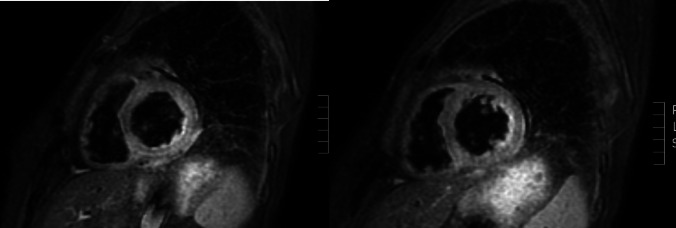

系统性硬化症(SSc)和淀粉样变是罕见的复杂疾病,损害多个器官的功能,每种疾病都有不同的致病机制:SSc的自身免疫和淀粉样变的错误折叠蛋白沉积。我们报告了第一例57岁女性并发SSc和系统性AL淀粉样变并多器官受累的病例,其中淀粉样变治疗导致SSc症状显著改善。患者于2023年夏季出现疲劳、用力性呼吸困难、上腹部疼痛和晕厥发作。调查显示左心室厚度轻度增加,NT-proBNP和肌钙蛋白升高,冠状动脉造影阴性。随后,她被诊断为SSc,多器官受累,活检证实为系统性AL淀粉样变。采用改良的Dara-CyBorD方案治疗可改善SSc症状,特别是在呼吸困难和皮肤受累方面。这是首次报道的SSc与系统性AL淀粉样变并存的病例。该患者对淀粉样变治疗反应良好,提示潜在的重叠治疗益处。多学科的方法是必不可少的,需要进一步的研究来探索这两种罕见疾病之间的治疗相互作用。

Systemic sclerosis (SSc) and amyloidosis are rare, complex conditions that impair the function of multiple organs, each with distinct pathogenic mechanisms: autoimmunity for SSc and misfolded protein deposition for amyloidosis. We present the first documented case of a 57-year-old woman with coexisting SSc and systemic AL amyloidosis with multi-organ involvement, in which treatment for amyloidosis led to a notable improvement in SSc symptoms. The patient presented experiencing fatigue, exertional dyspnea, epigastric pain and syncopal episodes in the summer of 2023. Investigations revealed mild increase in left ventricle thickness, elevated NT-proBNP and troponin with negative coronary angiography. She was subsequently diagnosed with SSc with multi-organ involvement and systemic AL amyloidosis confirmed by biopsy. Treatment with a modified Dara-CyBorD protocol led to improvement in SSc symptoms, especially in terms of dyspnea and skin involvement. This is the first reported case of SSc coexisting with systemic AL amyloidosis. The patient responded well to therapy for amyloidosis, suggesting potential overlapping treatment benefits. A multidisciplinary approach was essential, and further studies are needed to explore therapeutic interactions between these two rare diseases.